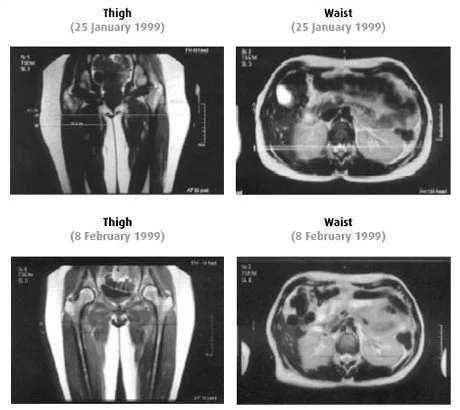

In a controlled study conducted Landeskrankenanstalten Salzburg, Magnetic Resonance Imaging (MRI) was used to measure and visually demonstrate the fat reduction achieved with HYPOXI-Training.

The test was conducted over a two week period, over which time the subjects carried out eight HYPOXI-Training sessions. In order to reliably measure the fat reduction over this time, an MRI was taken prior and then subsequent to the completion of the HYPOXI treatments.

Comparison of MRI scans showing thigh and waist images taken on January 25, 1999, and February 8, 1999.

It is apparent from these MR images that the thickness of the fat surrounding the subject’s lower body noticeably reduced on the completion of the HYPOXI-Training sessions.

These magnetic resonance images coupled with the table of average results below, confirm that the circumference loss achieved with HYPOXI is not attributed to fluid loss, but rather the result of real fat degradation.